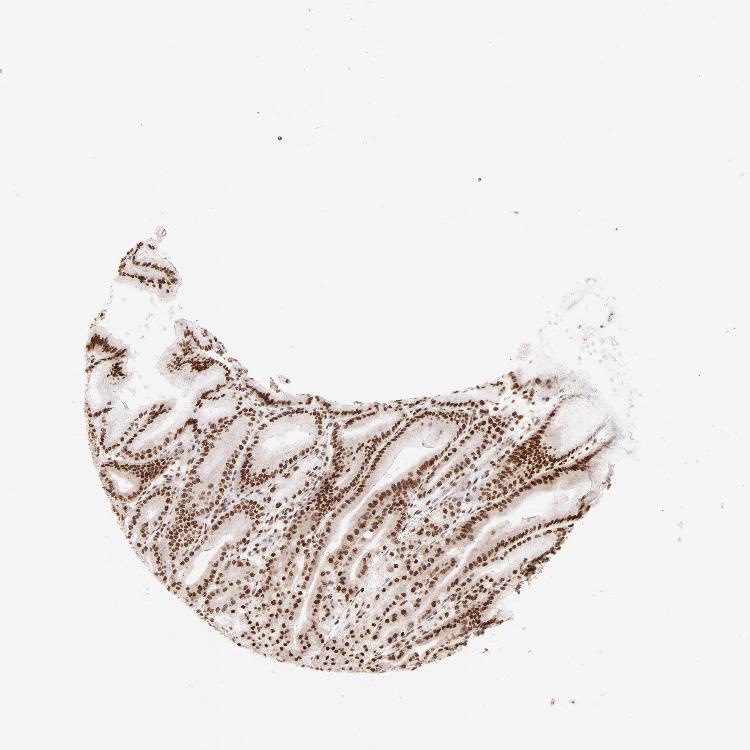

STOMACH 1 - Antibody stainingi

Antibody staining in the annotated cell types in the current human tissue is reported as not detected, low, medium, or high, based on conventional immunohistochemistry profiling in selected tissues. This score is based on the combination of the staining intensity and fraction of stained cells.

Each image is clickable and will lead to virtual microscopy that enables deeper exploration of all samples and also displays staining intensity scores, fraction scores and subcellular localization as well as patient and tissue information for each sample.

Antibody HPA017284Antibody CAB003703

Glandular cells LowHigh